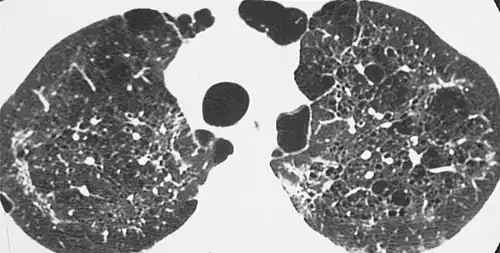

CT scan of the lung showing bullae in the lower lung lobes of a subject with type alpha-1-antitrypsin deficiency. There is also increased lung density in areas with compression of lung tissue by the bullae.